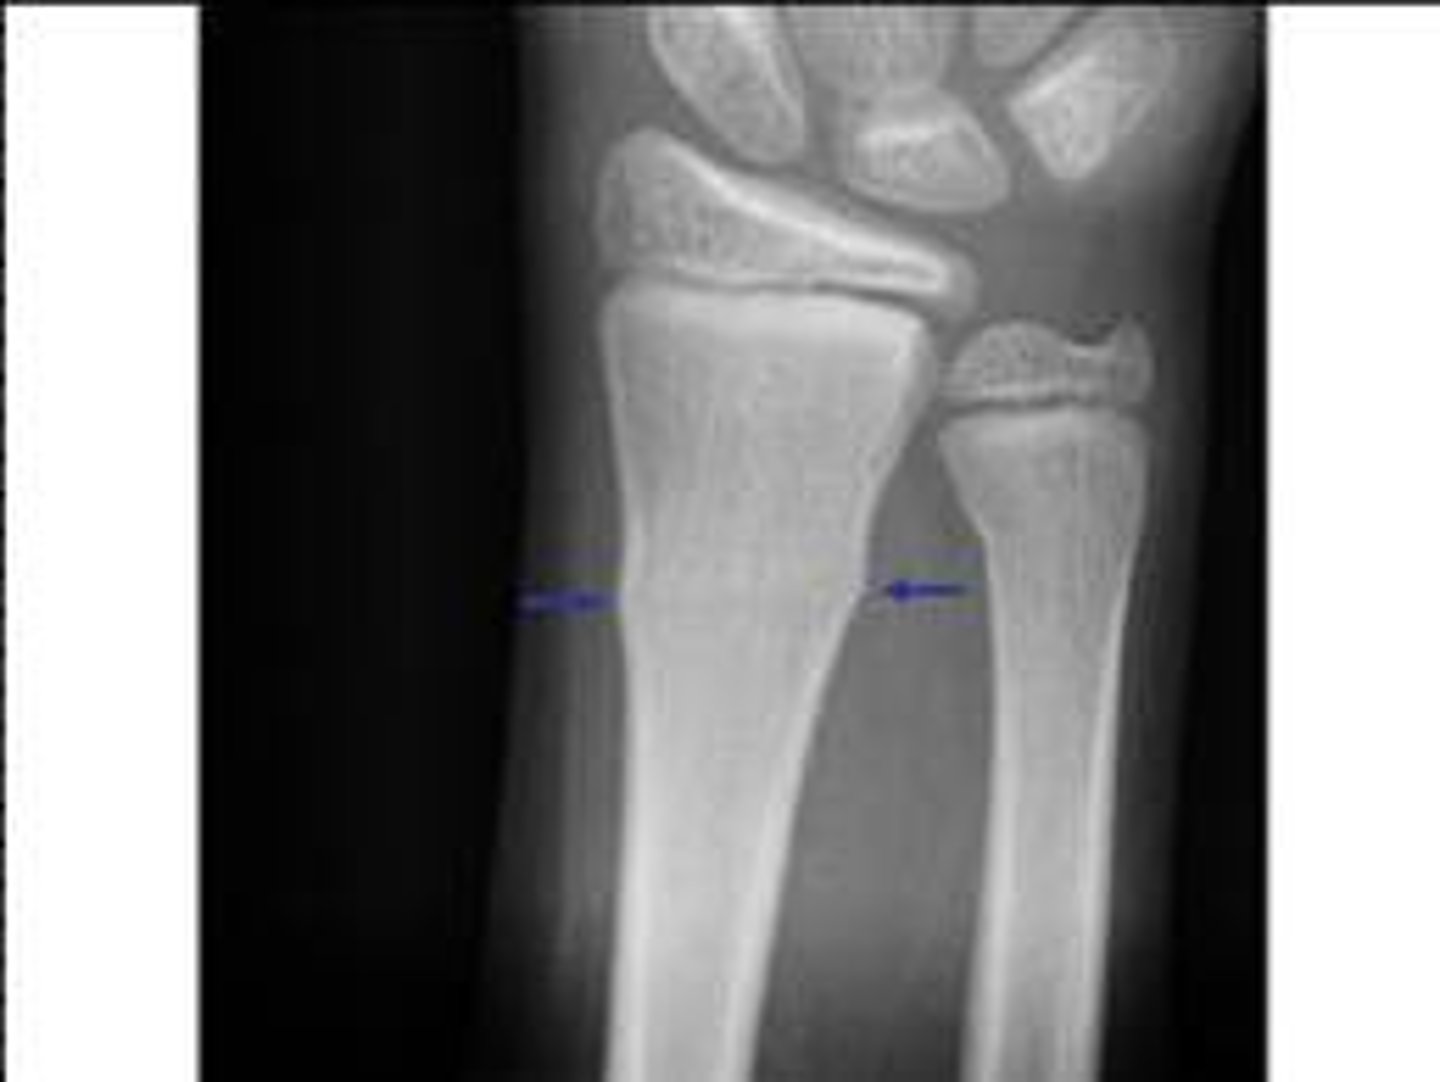

Difference between Colles and Smith fracture

Colles goes backwards (dinner fork)

Smith goes forwards